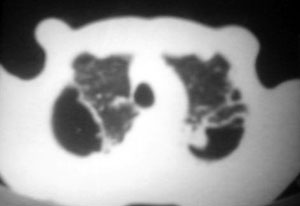

以下是引用逸风在2006-9-12 14:57:00的发言:[br]ct显示双肺上叶点片状及纤维索条状密度不均影,肺野外带近胸膜可见大小不等的含气空腔,壁略厚,境界清晰,未见液平面,中下肺野散在小片状及点状高密度影;纵隔内显示点状钙化,未见明显淋巴结肿大,构成胸廓诸骨未见明显异常.[br]诊断意见:1.双肺结核合并支气管播散;2.双肺上肺大泡.